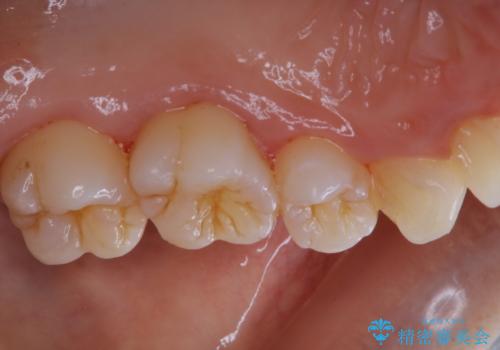

久々の来院で歯のクリーニング PMTC60分コース

- しばらく来院できなかったため、全体的にチェックとクリーニング希望でした。PMTC60分コースを行いました。

歯にステイン(着色)や歯石などが付着していると、汚れなのか虫歯なのかの判別が分かりにくく、正確な診断ができないことがあります。

そのため、定期的に専門的な機械や材料を使用したクリーニング(PMTC)をすることで、ご自身本来の歯の状態となります。より、健康なお口の維持をするためには、痛みや症状などが無くてもPMTCを行いお口の中の環境を綺麗にすることがおすすめです。